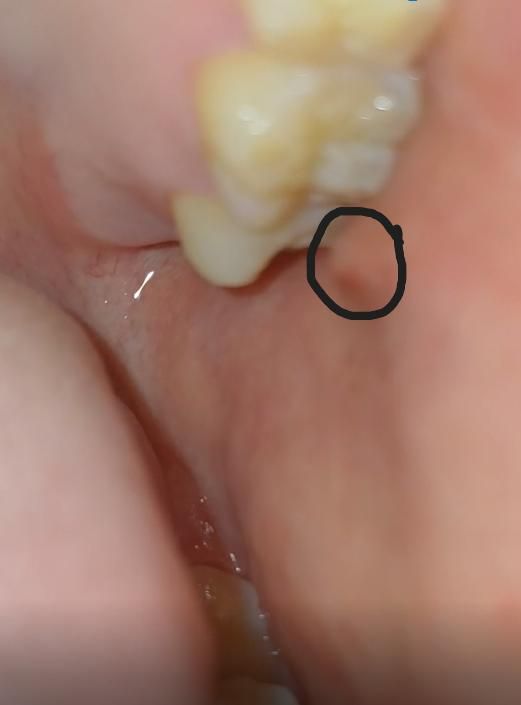

입안에 이빨옆쪽으로 부어올랐는데 뭘까요? 어디병원가야하죠

건들여도 딱히 아무런 통증도 없어요 왼쪽이 갑자기 이런데 딱히 이빨로 씹지도 않았고요

입 안열고 가만히 있으려고 해도 뭔가 부어올라서 그런가 불편하네요

• 1번 째 사진

사진으로 봤을 경우 구강 점막이 자극이 되어 붉게 된 것으로 생각됩니다. 음식을 먹을 때 너무 강한 힘으로 먹다보면 점막조직이 밀려. 치아 사이에서 씹히면서 사진과 같이 붉은색을 띨 수 있습니다. 해당 부위를 자극하지 않으면 대부분 일주일 정도 지나면 아물게 됩니다.

사진에 보이는건 볼살이 치아에 씹히거나 자극을 받아서 생기는겁니다. 큰 문제가 잇는건 아닙니다.

볼이 있는 부위라면 잘못씹히면서 부었을 가능성이 높습니다. 며칠 지나면 사라질겁니다.

타액선 염증이 있어 부었을 수도 있습니다 면역력저하, 컨디션이 안좋을 경우 일시적으로 그럴 수 있습니다